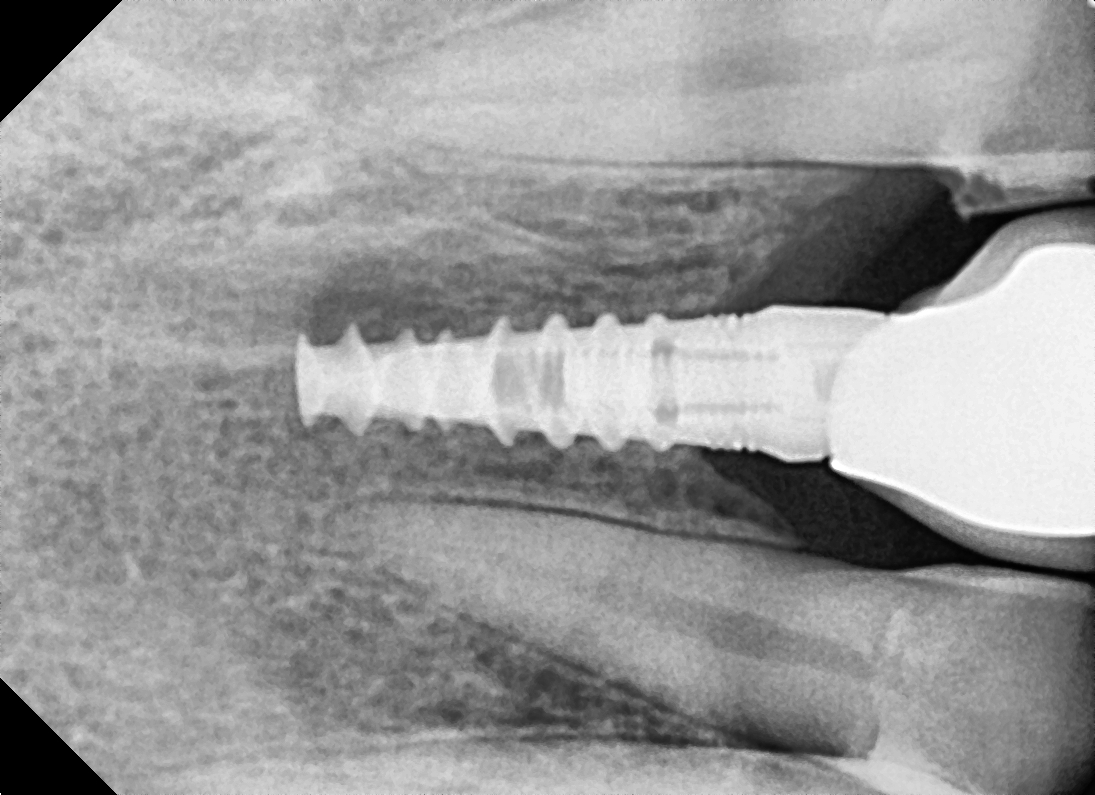

Images Of Dental Treatment Servcies Done At Our Hospital